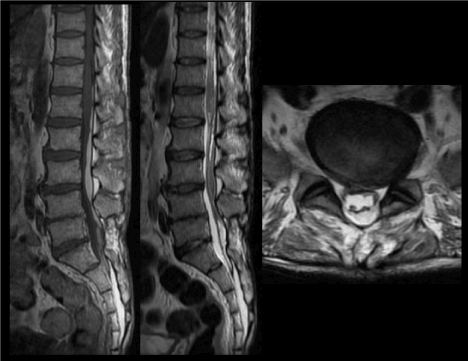

This is a rare complication following transforaminal epidural steroid injection and is characterized by clumping of the caudaequina nerve roots (Figure 8c), intrathecal fluid collection, enhancing nerve roots (Figures 8a and 8b) , pial and dural enhancement. “Empty sac” sign in patients with arachnoiditis is due to nerve roots adhering to the periphery of the dural sac.

Figure 8. (a,b)Sagittal T1-weighted images pre- and post gadolinium administration demonstrate abnormal enhancement of the cauda equina nerve roots, in keeping with arachnoiditis (c)Axial T1-weighted image post gadolinium administration shows abnormal enhancement of the clumped descending and exiting nerve roots